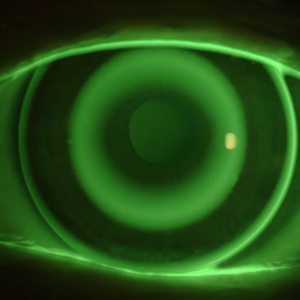

- umie ocenić dopasowanie soczewki na podstawie fluoresceiny i map topograficznych,

- Ocena fluoresceiny i map topograficznych